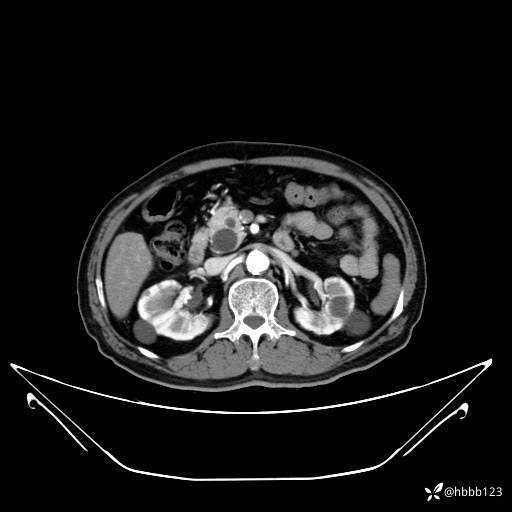

延迟期: